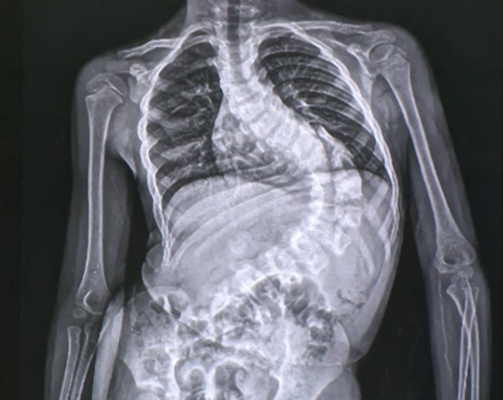

Lordose vs Cifose vs Escoliose: Comparação dos diferentes tipos de curvaturas da coluna vertebral

Escoliose Dextro e Levo: Compreender as diferenças nas direcções da curvatura da coluna vertebral

Saiba mais sobre as diferenças entre escoliose dextro e levo, dois tipos de curvatura da coluna vertebral, e [...]